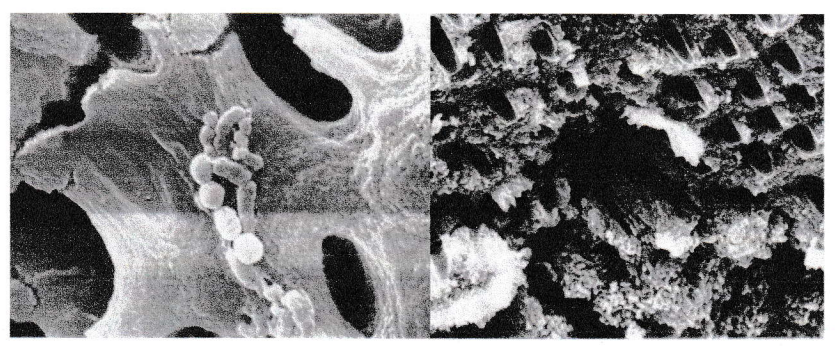

Bacilles et cocci sur la paroi canalaire et pénétrant les tubuli (microscope électronique à balayage).

Prevotella intermedia à l’entrée des tubuli (microscope électronique à balayage).